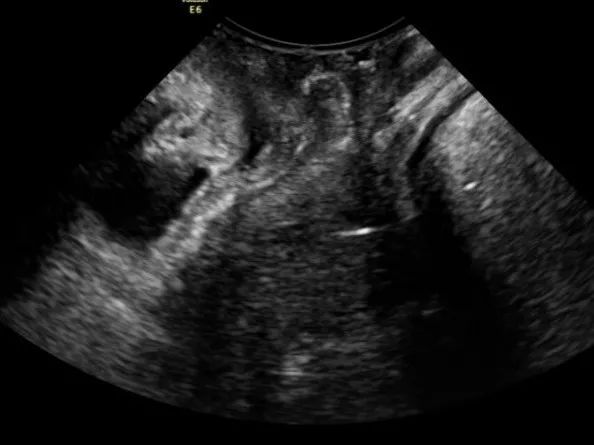

经过细致的盆底超声检查,医生确认王阿姨脱出来的“肿块”主要是膀胱的后壁,也就是所谓的Green III型膀胱脱垂;同时经过三维超声检查,王阿姨的耻骨直肠肌也没有明显的撕脱。根据超声结果,我院盆底疾病中心的医生为王阿姨定制了个性化的盆底治疗方案,现在王阿姨再也没有“肿块”的困扰了。

(静息状态)

(用力状态)